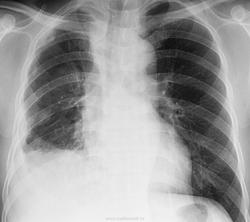

Асбест 1 ПА

Дата: 06/02/2004

Просмотров: 812